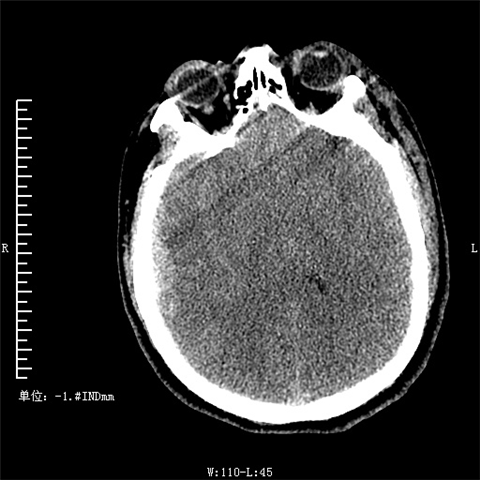

术前CT检查

术前CT:脑组织弥漫肿胀/脑室明显狭窄/环池显示不清楚。